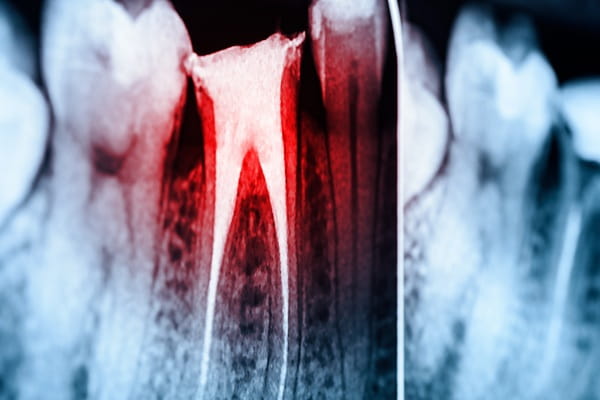

Root Canal

A root canal is a common dental procedure performed to treat an infected or damaged tooth. Inside each tooth, there is a soft tissue called pulp, which contains nerves, blood vessels, and connective tissue. When this pulp becomes infected or inflamed due to deep decay, repeated dental procedures, or a crack in the tooth, it can cause significant pain and discomfort.